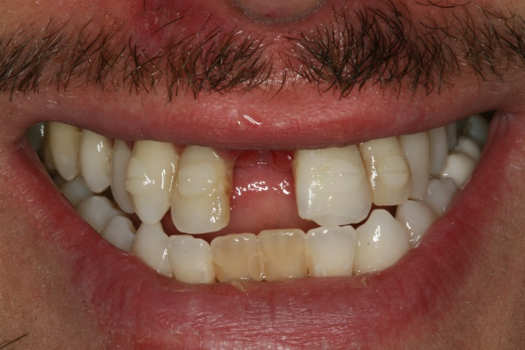

Case 2. Smile Zone Implant: Single Maxillary Central Incisor

Providing single-tooth restorations in the smile zone can be challenging; considerations for implant dentistry for a single maxillary incisor can be even more challenging. For this case, the digital workflow considerations were not much different from the previous case; radiographs, photography, and analog impressions were used. The patient was given alternative treatment options. He chose a single implant and final zirconia with cutback for porcelain application. The patient was advised about his surrounding vintage dentistry and told he should consider all maxillary anterior teeth, Nos. 6 through 11, be planned for better function and esthetics. The patient had the final say, which allowed the laboratory and the author to finalize the treatment plan with the definitive restoration.

Properly planning this case with digital dental technology offered a large quantity and quality of diagnostic information. Using the dental laboratory software to merge the entire 3D data set helped to predict the best outcome after the digital proposals for the implant abutment and final crown. The patient had been involved with implant dentistry and understood the value of technology available.

Figure 6 and Figure 7 depict a mature smile with many implant restorations. An analog impression was sent to the laboratory. The impression was scanned by the laboratory, a model was created virtually, and the implant dimensions and position were defined. The 3D surgical guide was fabricated (Figure 8), allowing the patient to receive his therapy swiftly and predictably. Tooth No. 8 was extracted, and the implant was placed and immediately loaded with an acrylic provisional treatment crown (Figure 9). The screw-retained treatment crown was fabricated in-office from a previously completed diagnostic wax-up.

Fig 6. Image of the patient’s mature smile.

Figure 6

Fig 9. Surgery day with immediately loaded implant and treatment crown.

Figure 9